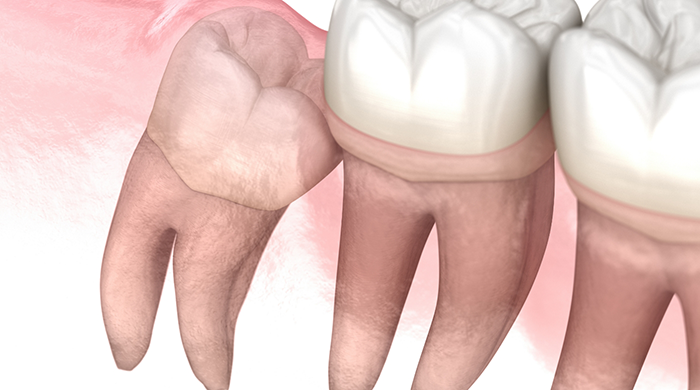

- The wisdom teeth may fail to erupt properly, instead being trapped underneath the gums. This is known as impaction.

- If wisdom teeth grow at an awkward angle, they can push against other teeth. Your bite may become misaligned, and pain and swelling may develop.